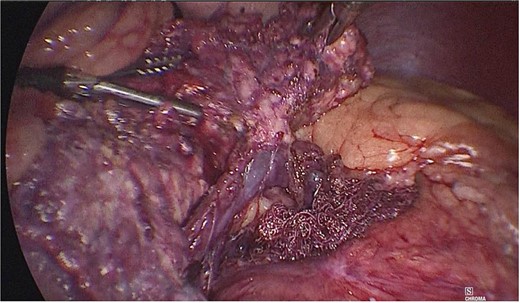

Dissection of the pancreas (body and tail) and splenic vascular structures (arteries and veins; Fig. 5). Intrapancreatic veins were identified. Dissection was performed with a harmonic scalpel of the pancreatic tissue of the vein, taking care not to disrupt it, and the dissection of vascular structures was completed, thus obtaining splenic preservation. The piece was removed, fibrin sealant was applied to the surgical site (Tisseel), and a drain was placed (Fig. 6). The patient had a satisfactory postoperative course and was discharged with a drain in place to be followed up in the outpatient clinic.

Dissection of the pancreas (body and tail) from splenic vascular structures (artery and vein).

Extraction of the anatomical piece preserving vascular structures.